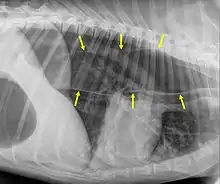

An x-ray of the thorax of a dog with megaoesophagus. The edges of the esophagus are shown by the yellow arrows. (In this image, the head end of the dog is to the right, and the tail end is to the left